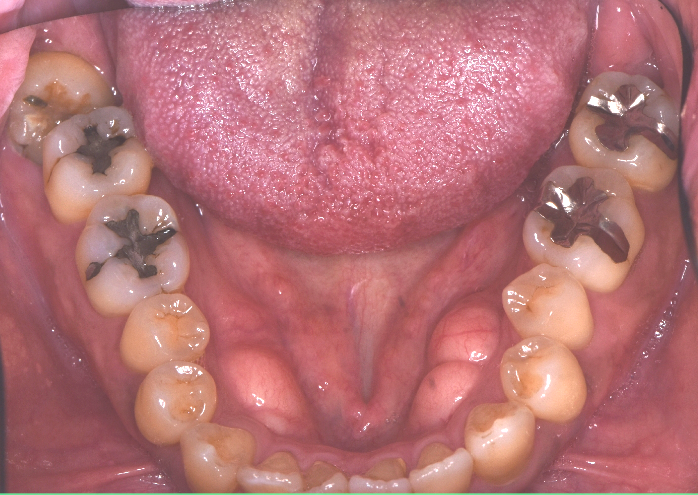

この方は、歯を削る量を最低限に!治療回数もなるべく減らしたい!とのご希望から、ダイレクトボンディングをご提案しました。この治療は型取りが必要ないので1回で治療を終えることができます^^

こちらの方は他の所にも銀歯がはいっており、治療が進むにつれ綺麗になり嬉しい!とお喜びいただきました。ダイレクトボンディングは長持ちしやすい治療ですが、強くかみ合わせる習慣がある方には別の症例をご提案することもあります。